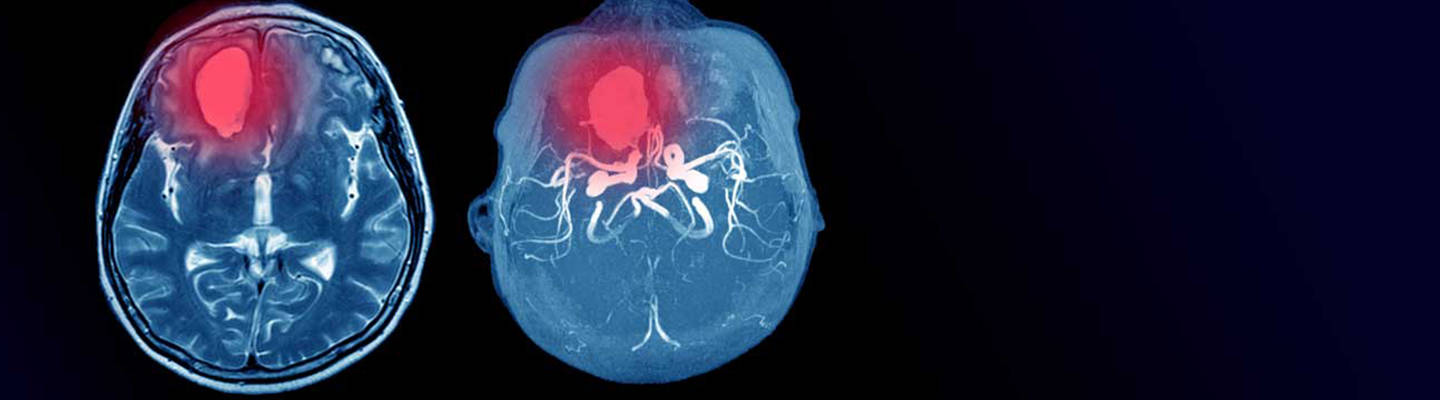

Image of brain scan

Providence offers one of the largest and most comprehensive cerebrovascular and endovascular programs in the Pacific Northwest. Our highly trained and experienced team includes cerebrovascular and endovascular neurosurgeons, neurologists and neurointerventional radiologists.

We partner with the award-winning Providence Stroke Center to treat cerebral aneurysms, AVMs, blood clots, intracranial and carotid stenosis and more. We are actively involved in research studies of new devices for the prevention and treatment of aneurysms and strokes.